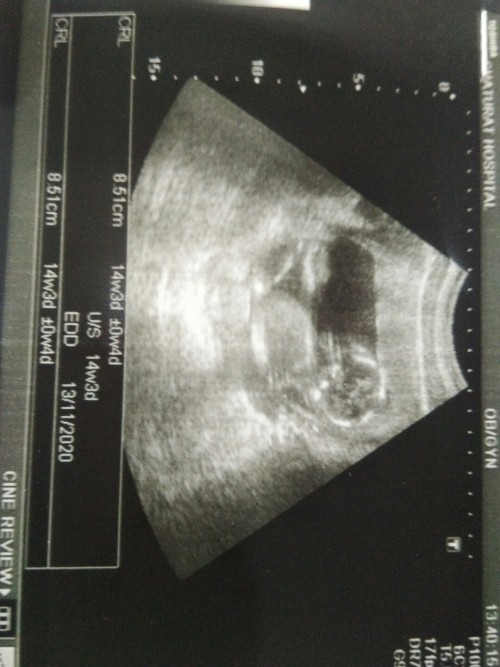

ตอน14w3dค่ะ